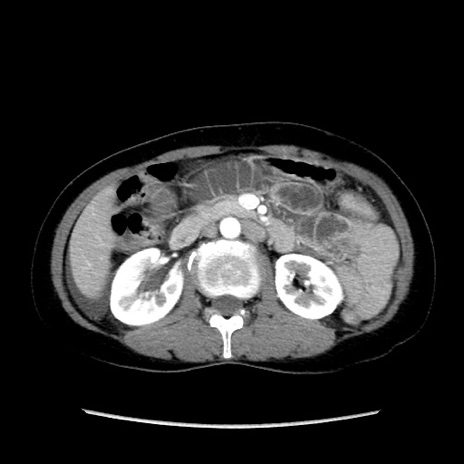

症例32(横断像)

【症例】40歳代 女性

【主訴】上腹部痛、嘔気・嘔吐

【現病歴】約9時間前頃から急に上腹部痛、嘔気、嘔吐が出現。改善しないため救急要請。

【既往歴】子宮頚癌(広汎子宮全摘術、放射線療法)、腸閉塞

【身体所見】腹部:平坦、軟、腸雑音亢進、上腹部を中心に腹部全体に圧痛あり。

【データ】WBC 8400、CRP 0.03